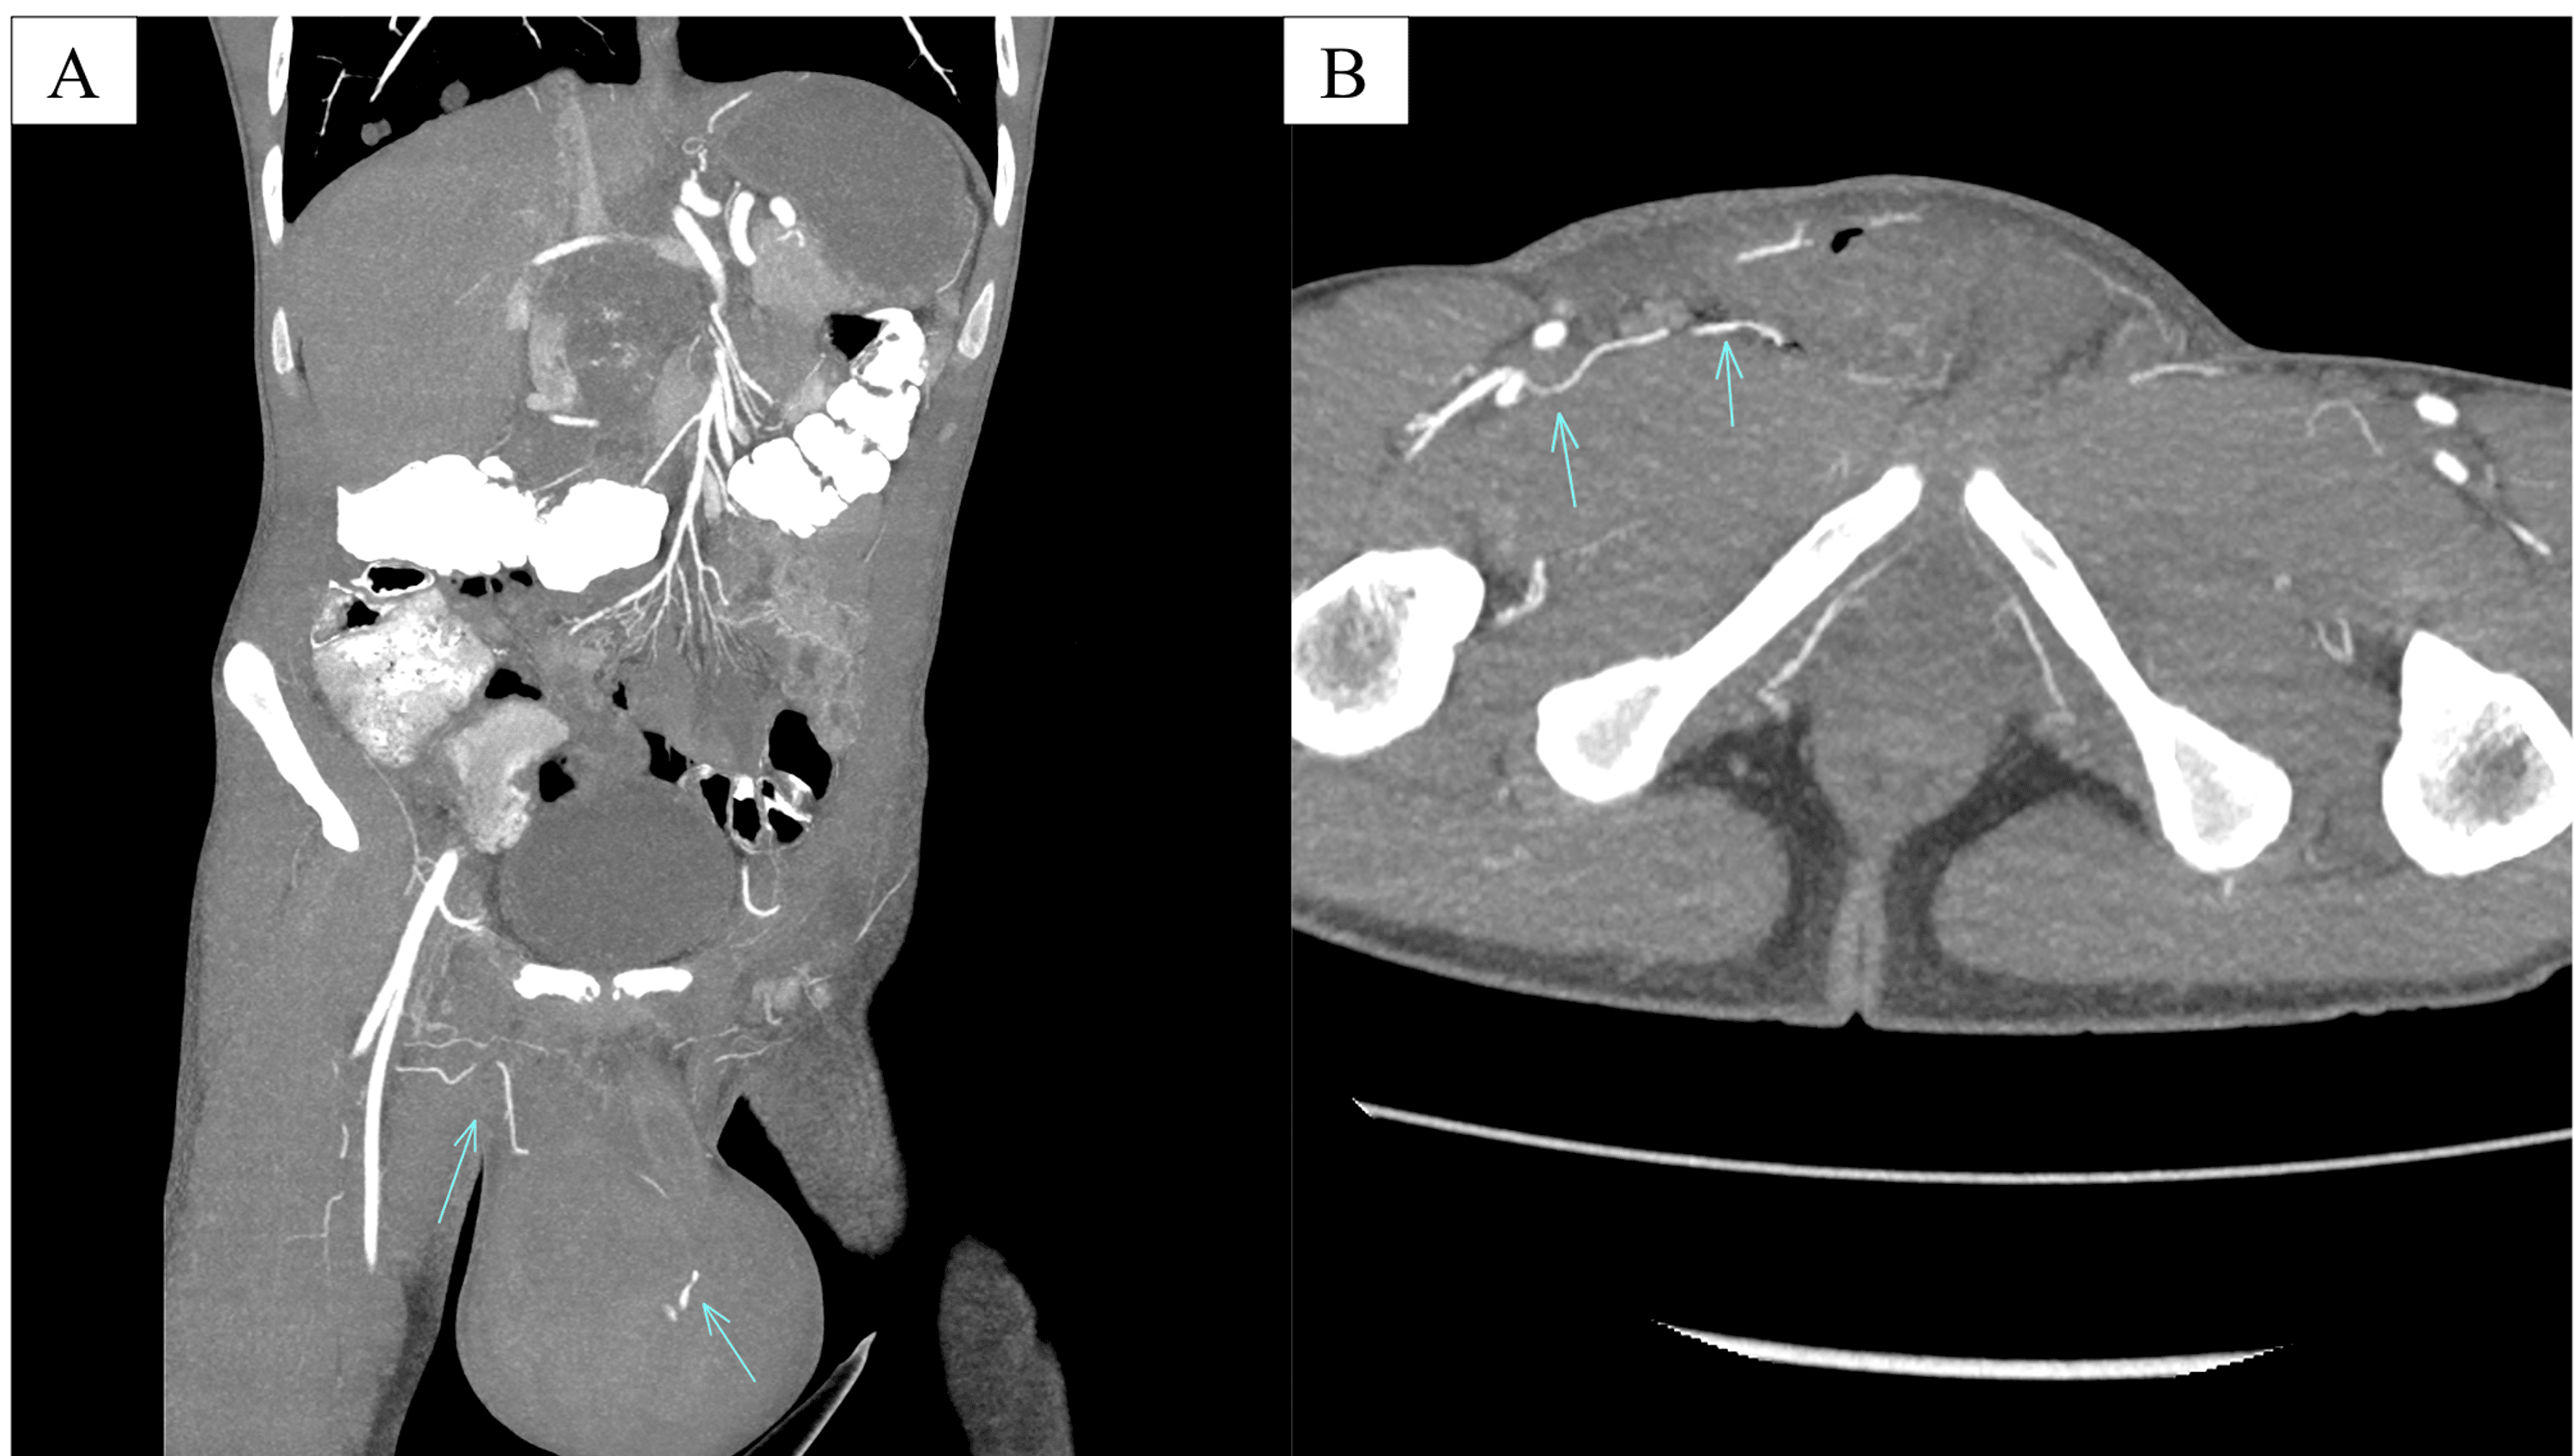

Cureus A Rare Case of Postorchidectomy Arterial Injury With Rapidly Enlarging Scrotal

Cureus A Rare Case of Postorchidectomy Arterial Injury With Rapidly Enlarging Scrotal Coil Embolization Scrotum  It redirects blood away from an enlarged vein in your scrotum. During the procedure the doctor makes a small nick in the skin, (usually in the groin). It redirects blood away from an enlarged vein in your scrotum. Varicocele embolization is a type of medical procedure. Varicocele embolization is a type of medical procedure. Varicocele embolization is a minimally invasive. Coil Embolization Scrotum.

Cureus A Rare Case of Postorchidectomy Arterial Injury With Rapidly Enlarging Scrotal Coil Embolization Scrotum  There are several options for the treatment of varicocele, including surgical repair either by open or microsurgical approach, laparoscopy, or. Coils are commonly used embolic for varicocele, and both detachable and pushable. During the procedure the doctor makes a small nick in the skin, (usually in the groin). Varicocele embolization is an outpatient procedure with a short recovery time. It. Coil Embolization Scrotum.

Cureus A Rare Case of Postorchidectomy Arterial Injury With Rapidly Enlarging Scrotal Coil Embolization Scrotum  During the procedure the doctor makes a small nick in the skin, (usually in the groin). Varicocele embolization is a type of medical procedure. Varicocele embolization is a minimally invasive procedure which is used to treat abnormal enlargement and dysfunctional veins which. It redirects blood away from an enlarged vein in your scrotum. Varicocele embolization is an outpatient procedure with. Coil Embolization Scrotum.

Cureus A Rare Case of Postorchidectomy Arterial Injury With Rapidly Enlarging Scrotal Coil Embolization Scrotum  It redirects blood away from an enlarged vein in your scrotum. During the procedure the doctor makes a small nick in the skin, (usually in the groin). Coils are commonly used embolic for varicocele, and both detachable and pushable. It redirects blood away from an enlarged vein in your scrotum. There are several options for the treatment of varicocele, including. Coil Embolization Scrotum.

Cureus A Rare Case of Postorchidectomy Arterial Injury With Rapidly Enlarging Scrotal Coil Embolization Scrotum  Varicocele embolization is a type of medical procedure. It redirects blood away from an enlarged vein in your scrotum. Varicocele embolization is an outpatient procedure with a short recovery time. Coils are commonly used embolic for varicocele, and both detachable and pushable. It redirects blood away from an enlarged vein in your scrotum. During the procedure the doctor makes a. Coil Embolization Scrotum.

Cureus A Rare Case of Postorchidectomy Arterial Injury With Rapidly Enlarging Scrotal Coil Embolization Scrotum  During the procedure the doctor makes a small nick in the skin, (usually in the groin). Varicocele embolization is a type of medical procedure. It redirects blood away from an enlarged vein in your scrotum. Varicocele embolization is a minimally invasive procedure which is used to treat abnormal enlargement and dysfunctional veins which. There are several options for the treatment. Coil Embolization Scrotum.

Cureus A Rare Case of Postorchidectomy Arterial Injury With Rapidly Enlarging Scrotal Coil Embolization Scrotum  Varicocele embolization is a minimally invasive procedure which is used to treat abnormal enlargement and dysfunctional veins which. Coils are commonly used embolic for varicocele, and both detachable and pushable. There are several options for the treatment of varicocele, including surgical repair either by open or microsurgical approach, laparoscopy, or. During the procedure the doctor makes a small nick in. Coil Embolization Scrotum.

Cureus A Rare Case of Postorchidectomy Arterial Injury With Rapidly Enlarging Scrotal Coil Embolization Scrotum  Varicocele embolization is an outpatient procedure with a short recovery time. Coils are commonly used embolic for varicocele, and both detachable and pushable. There are several options for the treatment of varicocele, including surgical repair either by open or microsurgical approach, laparoscopy, or. During the procedure the doctor makes a small nick in the skin, (usually in the groin). It. Coil Embolization Scrotum.